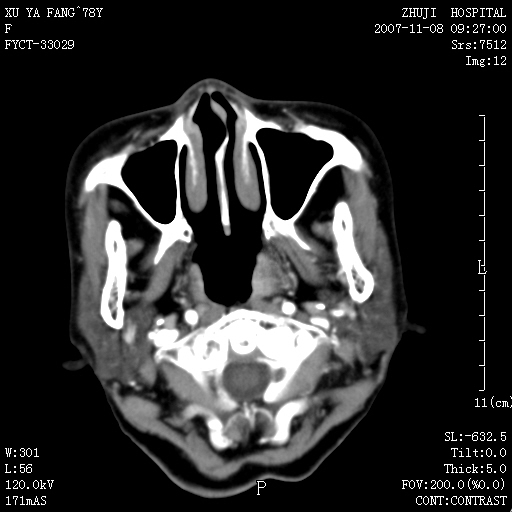

女性,78y,发现左侧扁桃体区肿大,表面糜烂.及颈部肿块一周.

左侧扁桃体恶性肿瘤伴淋巴结的转移;考虑为扁桃体癌可能。此部位的恶性肿瘤以扁桃体癌和淋巴瘤多见,相对来说淋巴瘤范围较广泛些。有时两者区别较难,需要活检。

左侧扁桃体区软组织占位,强化后边界清晰,密度均匀,周围脂肪间隙清晰。周围淋巴结肿大。首先考虑扁桃体炎性增生,不排除扁桃体区的恶性肿瘤!!不知临床上有无发烧??/wbc是否增高??

左侧口咽侧壁巨大软组织肿块突入口腔,增强密度均匀,中度增强,左颈部多发肿大淋巴结,考虑左侧扁桃体恶性肿瘤(淋巴瘤还是癌不好鉴别)并淋巴结转移。 期待病理!

结果淋巴瘤-----学习了